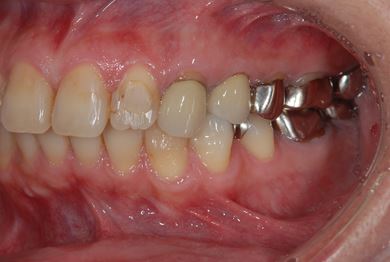

| 性別/年齢 | 女性 / 46歳 | ||||||||||||||||||||||||||||||||

| 主訴 | 歯ぐきがただれてる。歯が少しうずく。 | ||||||||||||||||||||||||||||||||

| 治療方針 | インプラント治療にて、機能的・審美的回復を行う。 | ||||||||||||||||||||||||||||||||

| 治療内容 | インプラント1本(GBR)、ハイブリッドセラミック1本 | ||||||||||||||||||||||||||||||||